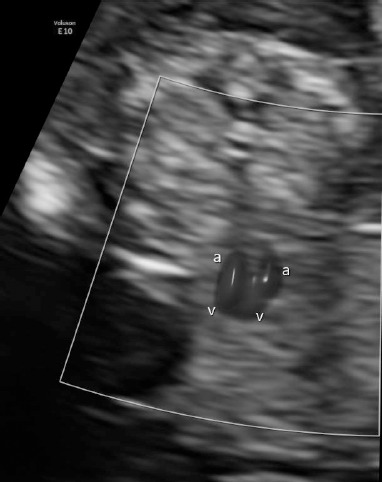

A thirty-three-year-old pregnant woman in her second pregnancy (the first pregnancy was unsuccessful – miscarriage at week 8 of pregnancy), visited a gynecologist for a routine check-up at week 12 of pregnancy, during which developmental disorders were found in the anterior chest cavity and abdominal walls. The woman was healthy, denied having chronic diseases, and was taking folic acid and vitamin preparations for pregnant women. The patient also denied the existence of any infections at an early stage of pregnancy. The woman was referred to the Laboratory of Prenatal Research, where, during prenatal ultrasound examination, the fetus was diagnosed with a complex defect of the skin and division of the body’s cavities in the form of pentalogy of Cantrell. The fetus was diagnosed with umbilical cord omphalocele (Figure 1), diaphragmatic hernia with diaphragmatic defect, sternal defect, ectopic heart and pericardial defect (Figures 2-3).

Moreover, the fetal heart seemed to possess four cavities, two slightly asymmetrical inflows of the ventricles and the origins of two vessels in abnormal relationships were visualized (Figures 4-5).